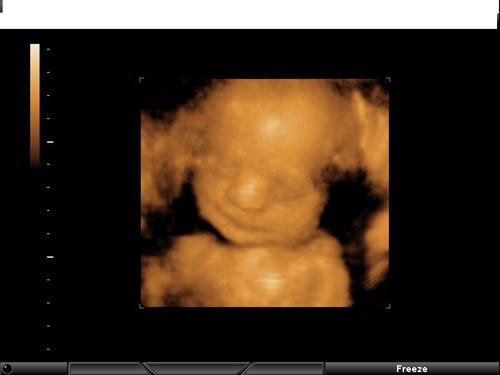

Yesterday was my 3rd wedding anniversary, and we decided to go see our little girl in 3D style... so awesome!

Here's a picture of my little princess:

MRSRBK.. that sono picture is just too adorable for words!!

Had my first growth sono today, baby is measuring on target! So now instead of having to go back at 32 weeks and then 36 weeks to check, they have me coming back at 35 weeks. The tech also gave us a couple of 3D images of which I'll post later. The detail is MUCH better than what I posted. She definately looks just like my husband. She must also have good dreams (unlike her mommy!) because as we were watching the screen, she started to smile.